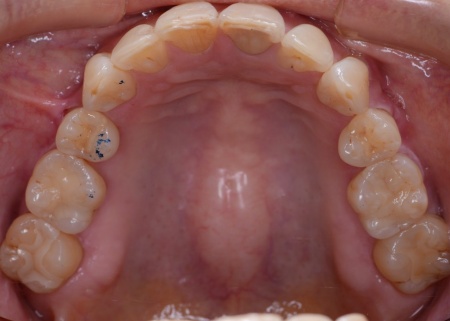

60代女性 すきっ歯が目立つ噛み合わせをワイヤー矯正とアライナー矯正の併用で改善した症例

拝見したところ、前歯に隙間が空いており、いわゆるすきっ歯の状態でした。

患者様は、歯並びと噛み合わせの根本的な改善を希望されています。

そのため、ワイヤー矯正である程度歯の移動を行ったのち、アライナー矯正(マウスピース矯正)で仕上げを行う矯正治療を提案し、同意いただきました。

2種類の矯正を組み合わせることで、歯をしっかり移動させながら、治療期間の短縮が望めます。

まずはワイヤー矯正を行い、ある程度まで歯並びを整えます。

その後アライナー矯正に移行し、正しい歯並びになるよう調整を行いました。

最後に、噛み合わせや前歯の隙間が改善されたことを確認して、治療を終了しています。